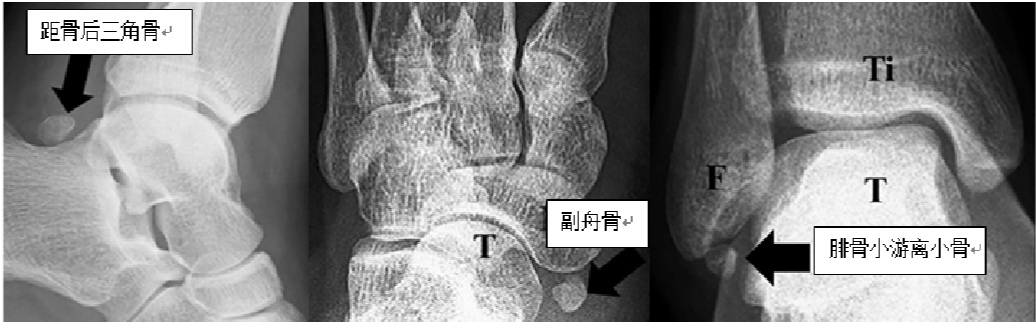

按照其成因,有骨化中心的骨均可以形成副骨,四肢骨多见,其中下肢相对于上肢比较常见,尤其在足踝部。正常人足部有30多种副骨,一般人群中足踝副骨的发病率为18%~36.3%。比较常见的如副舟骨(发病率4%~21%)、距骨后三角骨(发病率1%~25%)、腓骨下游离小骨(发病率0.2%~6.6%)。

其二,副骨形成的部位狭小,在活动过程中与邻近骨或肌腱软组织之间的摩擦、撞击、挤压,导致滑囊炎和肌腱炎,引起疼痛。如距骨后三角骨在踮起脚尖动作下会被上方的胫骨与下方的跟骨挤压,就如夹核桃一样(如下图),产生疼痛,这种情况多见于运动员、芭蕾舞者。

其三,副骨有肌腱或韧带附着,当发生扭伤或者反复的运动时,副骨与正常骨之间的纤维软骨可能发生联合撕裂,引起副骨不稳定,进而出现关节不稳。例如腓骨下游离小骨,部分会附着踝关节外侧韧带,踝扭伤后会出现踝关节不稳症状。